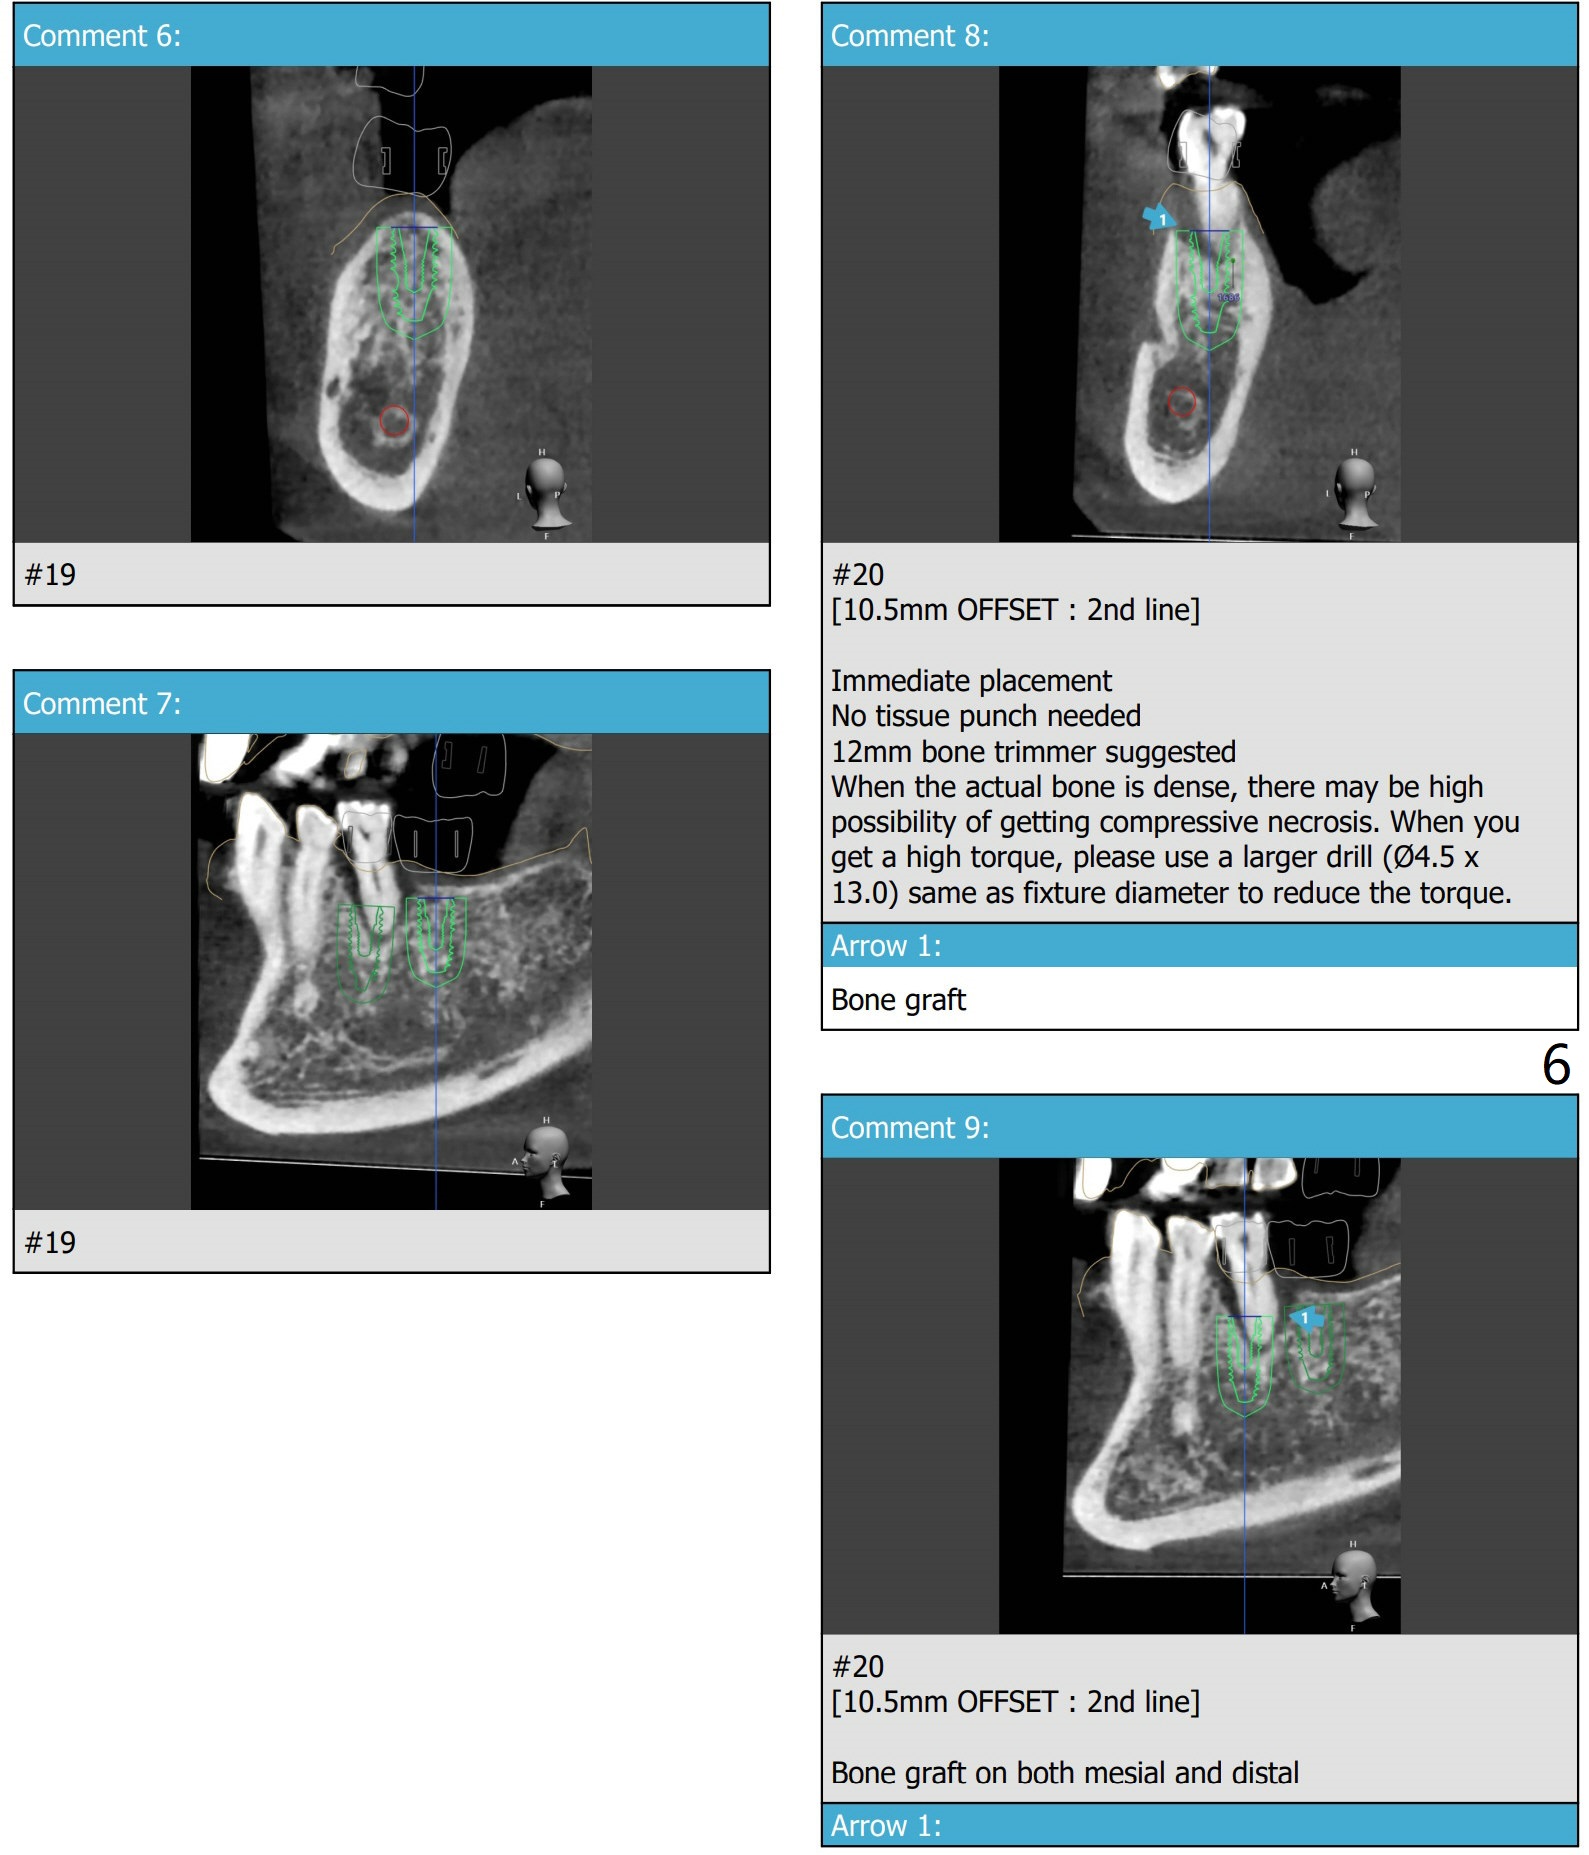

#14 Indistinct Buccal Plate

A 80-year-old man requests implants to replace his missing teeth. #14 incision for bone graft. PRFx2. Tatum 14 mm for #14 and 19, 14 or 17 mm for 20. Prepare taps.